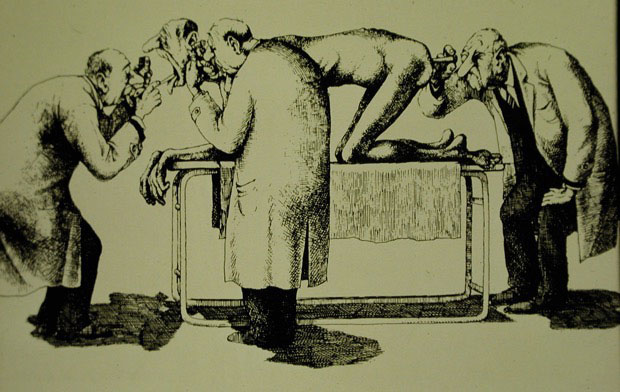

Endoskopi Nedir?

Vücudun doğal boşluklarına esnek ve ince bir kamerayla bakma işine endoskopi adı verilir. Endoskopi nereye uygulanıyorsa oranın adını alır. Yemek borusunun incelemesine “özofagoskopi”, mideninkine “gastroskopi” ve onikiparmak bağırsağının incelenmesine ise “duodenoskopi” denir.

NASA uzay teknolojileri sayesinde, fiberoptiklerin gelişmesiyle endoskoplar inceldi ve esnek hale geldi. Kliniğimizde kullanılan endoskoplar 5-7 mm inceliğindedir.

Endoskopi İşlemi Hissedilir mi?

Hastaların en büyük korkusu, endoskopi sırasında yapılanları hissedeceklerini düşünmeleridir. İşleme başlamadan önce hastanın önce boğazı uyuşturulur, daha sonra verilen ilaçlarla hasta uyutulur. Hasta uyumasına ragmen bu anestezi değildir. İşlem sırasında olanları duymayan hasta işlemi de hatırlamaz.

Endoskopi Şart mıdır?

Endoskopi sırasında elde edilen bilgiler başka hiçbir yöntemle elde edilemez. Endoskopinin olmadığı dönemlerde hastalara röntgen filmleri çekilirdi, fakat bu yöntem sindirim sistemi hastalıklarının tanısını koymada yetersizdir. Endoskopide elde edilen görüntüler sizing hastalığınızın kanıtını oluşturacağı için yanlış tedavilerin de önüne geçilir.

Yüksek çözünürlük (HD) en yeni kuşak cihazlarda mevcuttur. Dokuları daha iyi görmeyi ve ayrıntıları yakalamayı sağlar. Narrow Band Imaging (NBI) ise normal ışık dalga boylarını değiştirerek görüntü elde etmeyi sağlar; NBI ile daha derinlemesine görüntü elde edilir.